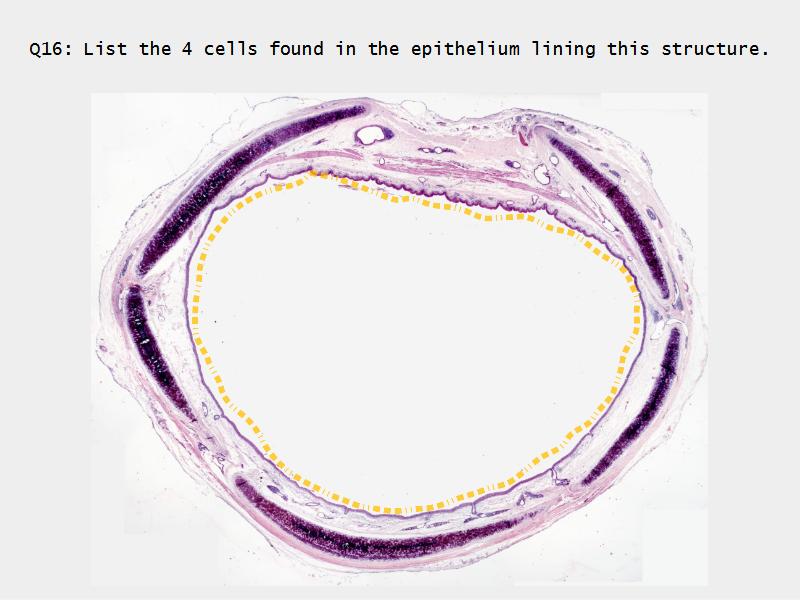

Respiratory epithelium

- Pseudostratified

- Ciliated

- Columnar

- Epithelium with

- 4 Cells

- Ciliated columnar cells

- Non-ciliated columnar cells

- Goblet cells

- Basal cells

Trachea